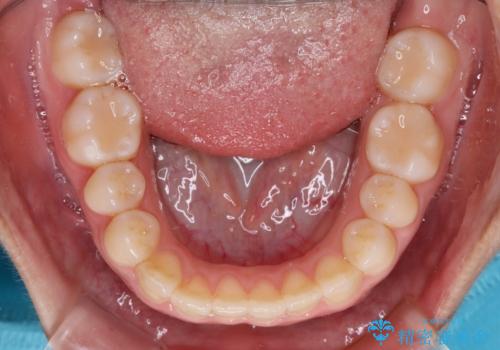

前歯のクロスバイトを改善 インビザライン・モデレートによる矯正治療

- 上下前歯のクロスバイトと叢生を気にして来院された患者様です。

インビザラインでの治療を希望されていて、デコボコの程度が中等度であり、安価なパッケージにて対応可能と判断されたため、インビザライン・モデレートを用いて矯正治療を行うこととしました。